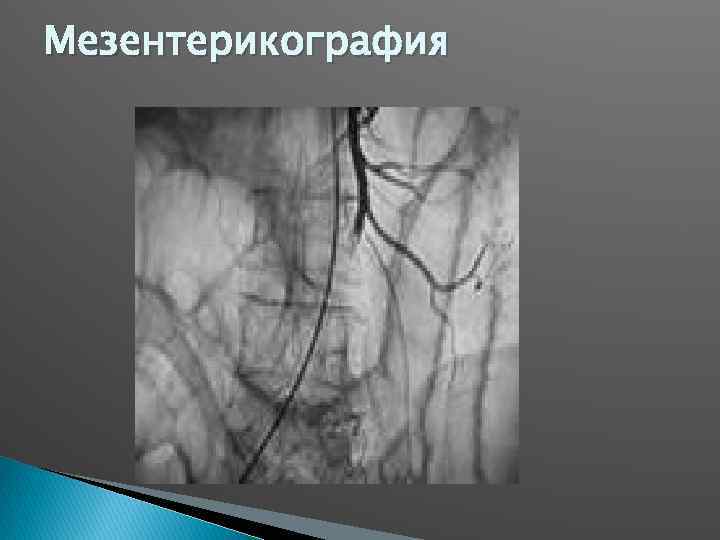

Мезентерикография

Мезентерикография